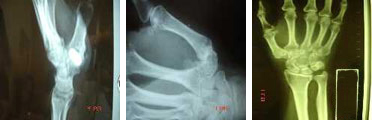

Artrosis trapecio-metacarpiana

Sin lugar a dudas, la artrosis trapecio-metacarpiana es la más frecuente de la mano y de amplia presencia en el sexo femenino a partir de los cincuenta años. Se ubica entre el trapecio y el primer metacarpiano y limita los movimientos de la pinza y oposición del pulgar.

Existen diferentes técnicas quirúrgicas para solucionar esta patología cuando está evolucionada y los tratamientos conservadores no son efectivos: desde la resección del trapecio parcial o completa y la colocación de una plastia tendinosa de diferentes formas a la colocación de una prótesis articular en la zona dañada. Existen también modelos de prótesis a poder implantar.

El resultado en cualquiera de estos supuestos es muy satisfactorio pudiendo restituirse la función de la mano a partir de las 4 semanas.